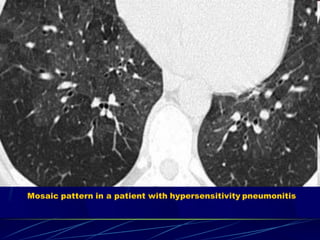

Mosaic attenuation

The term 'mosaic attenuation' is used to describe density

differences between affected and non-affected lung areas.

Lung density and attenuation depends

partially on amount of blood in lung tissue.

May be due to

 vascular obstruction,

 abnormal ventilation or

 airway disease

Mosaic pattern in a patient with hypersensitivity pneumonitis